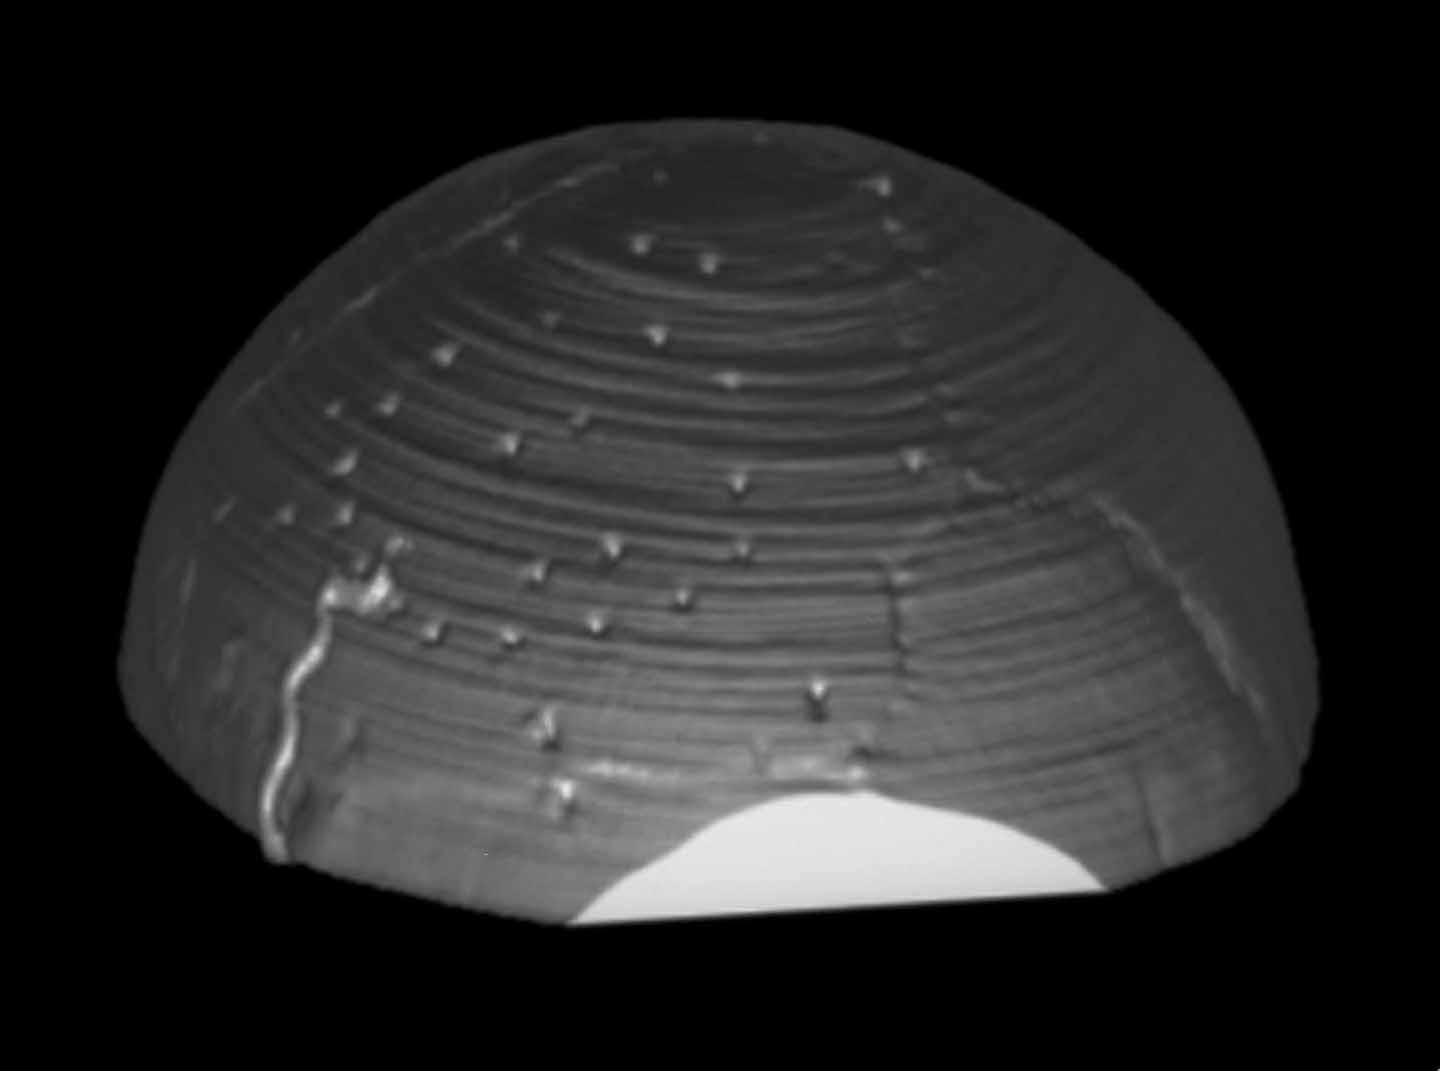

Demolizione/ricostruzione

cranica in un unico tempo |

Cranioplastiche |

Ricostruzioni

craniche complesse |

| Meningioma

con demolizione-ricostruzione della teca cranica in un unico tempo

con tecnica microchirurgica e neuronavigazione. |